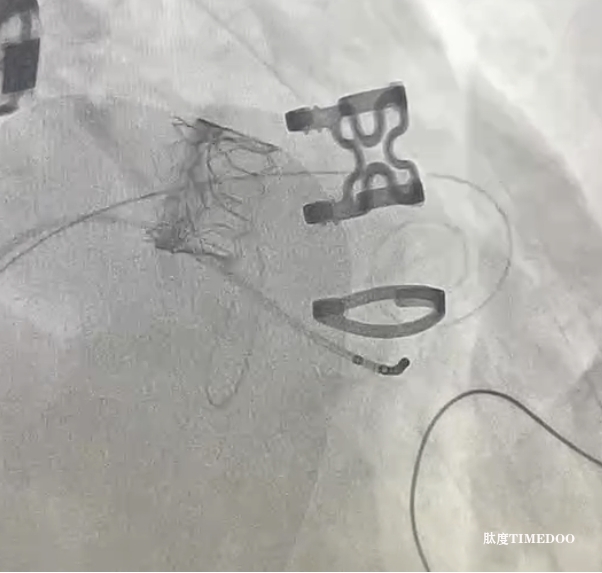

植入的新瓣膜。

3月31日,陳樣新等通力合作,為龍伯成功實(shí)施了“二尖瓣瓣中瓣植入術(shù)”。由于患者原生物瓣前葉較長,為盡量減少對流出道的影響,團(tuán)隊(duì)采用國際先進(jìn)的Lampoon(瓣葉切割)技術(shù),在體內(nèi)精準(zhǔn)切割二尖瓣前葉,使新瓣膜植入后不易對流出道產(chǎn)生影響,同時(shí)大大提高了新瓣膜的貼合度。

經(jīng)過近2小時(shí)的精準(zhǔn)操作,新的瓣膜穩(wěn)穩(wěn)地植入衰敗的瓣環(huán)上。術(shù)中心臟超聲顯示,二尖瓣返流幾乎完全消失,瓣口面積2.3平方厘米,跨瓣壓差為4毫米汞柱,瓣膜功能良好?!俺R?guī)的二次開胸外科瓣膜置換手術(shù),對龍伯這類老年患者風(fēng)險(xiǎn)極大,不僅手術(shù)復(fù)雜,還可能出現(xiàn)多種嚴(yán)重并發(fā)癥?!标悩有抡f。